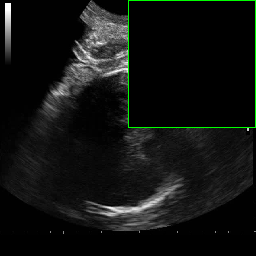

In practical clinical settings, medical images are often incomplete or degraded due to occlusions, artifacts, or limited fields-of-view. Therefore, a reliable segmentation model must be robust to missing spatial context and capable of inferring anatomical structures from partially observed inputs. To evaluate this critical property, we conducted a masking experiment using the FH-PS-AoP dataset. In this experiment, we systematically removed one quadrant from the input image, top-left, top-right, bottom-left, or bottom-right, and evaluated the performance of DAUNet compared to the baseline UNet.

Figure 7 presents a comprehensive visual comparison of the predicted offset maps and segmentation masks under each masking condition. The first column shows the original (unmasked) input along with its corresponding predictions, while subsequent columns depict the results for each of the masked quadrants.

DAUNet demonstrates markedly higher resilience to missing context compared to UNet. Its predicted offset maps remain dense and structured, with vectors that preserve anatomical directionality even when significant regions of the input are absent. This behavior reflects DAUNet’s ability to infer context from the remaining visual cues. In contrast, UNet exhibits sparse or disoriented offsets in the masked scenarios, indicating reduced spatial awareness and compromised localization.

To better understand this phenomenon, we analyzed the receptive fields of both models. For a representative pixel, we visualized its corresponding receptive area contributing to the output. In UNet, the receptive field is fixed and grid-constrained (refer to second row of Figure 7), making it sensitive to occlusions. On the other hand, DAUNet leverages deformable convolutions to dynamically adjust its receptive field based on the visible content. This adaptability is evident in the red and white arrows in the fourth column of Figure 7, where DAUNet modifies its offset patterns to account for the masked input.

The segmentation masks in third and fifth rows of Figure 7, further substantiate these findings. DAUNet consistently produces anatomically plausible segmentations of both the fetal head (green) and pubic symphysis (red), with minimal degradation even under 25% missing input. The output contours remain smooth, accurate, and well-aligned with ground truth boundaries. In contrast, UNet’s performance deteriorates noticeably, with fragmented or distorted segmentations, especially around the fetal head, as indicated by white arrows in the figure.

These results highlight the efficacy of DAUNet’s architectural innovations. The proposed combination of deformable convolution and SimAM attention allows the model to effectively reason over the visible context and compensate for spatial omissions. This robustness to incomplete inputs makes DAUNet well-suited for deployment in real-world medical environments, where noise, occlusions, and partial data are common challenges.